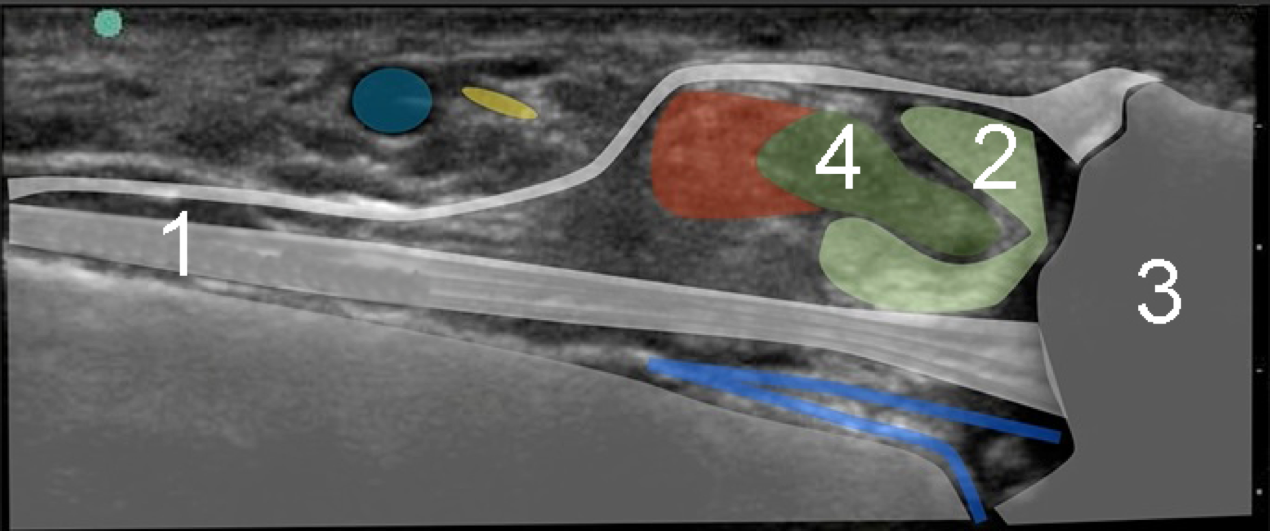

1. Fibulocalcaneal Ligament

2. Peroneus Brevis

3. Malleolus

4. Peroneus Longus